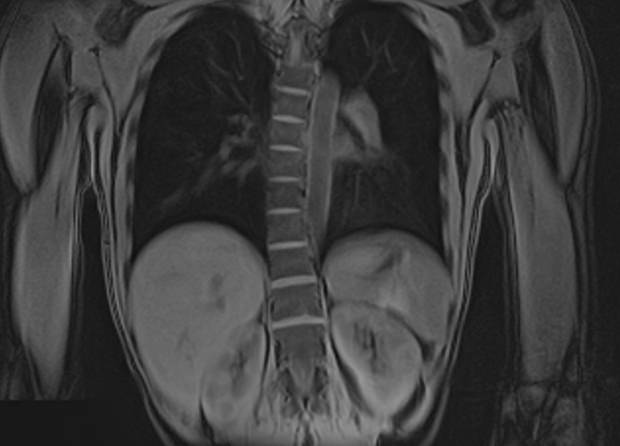

Скрининговое обследование всего тела с помощью метода магнитно-резонансной томографии включает в себя сканирование головы, шеи и туловища с органами брюшной полости, забрюшинного пространства и малого таза.

• органов, расположенных в забрюшинном пространстве (почки, надпочечники, мочеточники);

• органов малого таза (мочевой пузырь, прямая кишка, матка и яичники у женщин, предстательная железа и семенные пузырьки у мужчин);